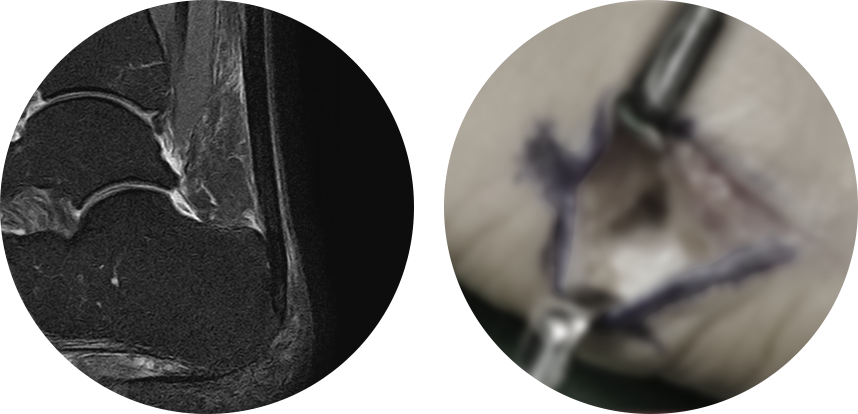

비수술적으로 치료가 되지 않는 만성 족저근막염에 대한 치료로, 2mm 정도의 소형 관절 내시경을 이용하여

족저근막을 부분 유리하여 수술 후 통증이 적고 일상생활로의 회복이 빠릅니다.

MRI 사진의 빨간 포탈을 이용하여 족저근막을 유리하여 터놓은 후, 시간이 지나면서 자연스럽게 연결되어 늘어나는 효과가 나타나게 됩니다.